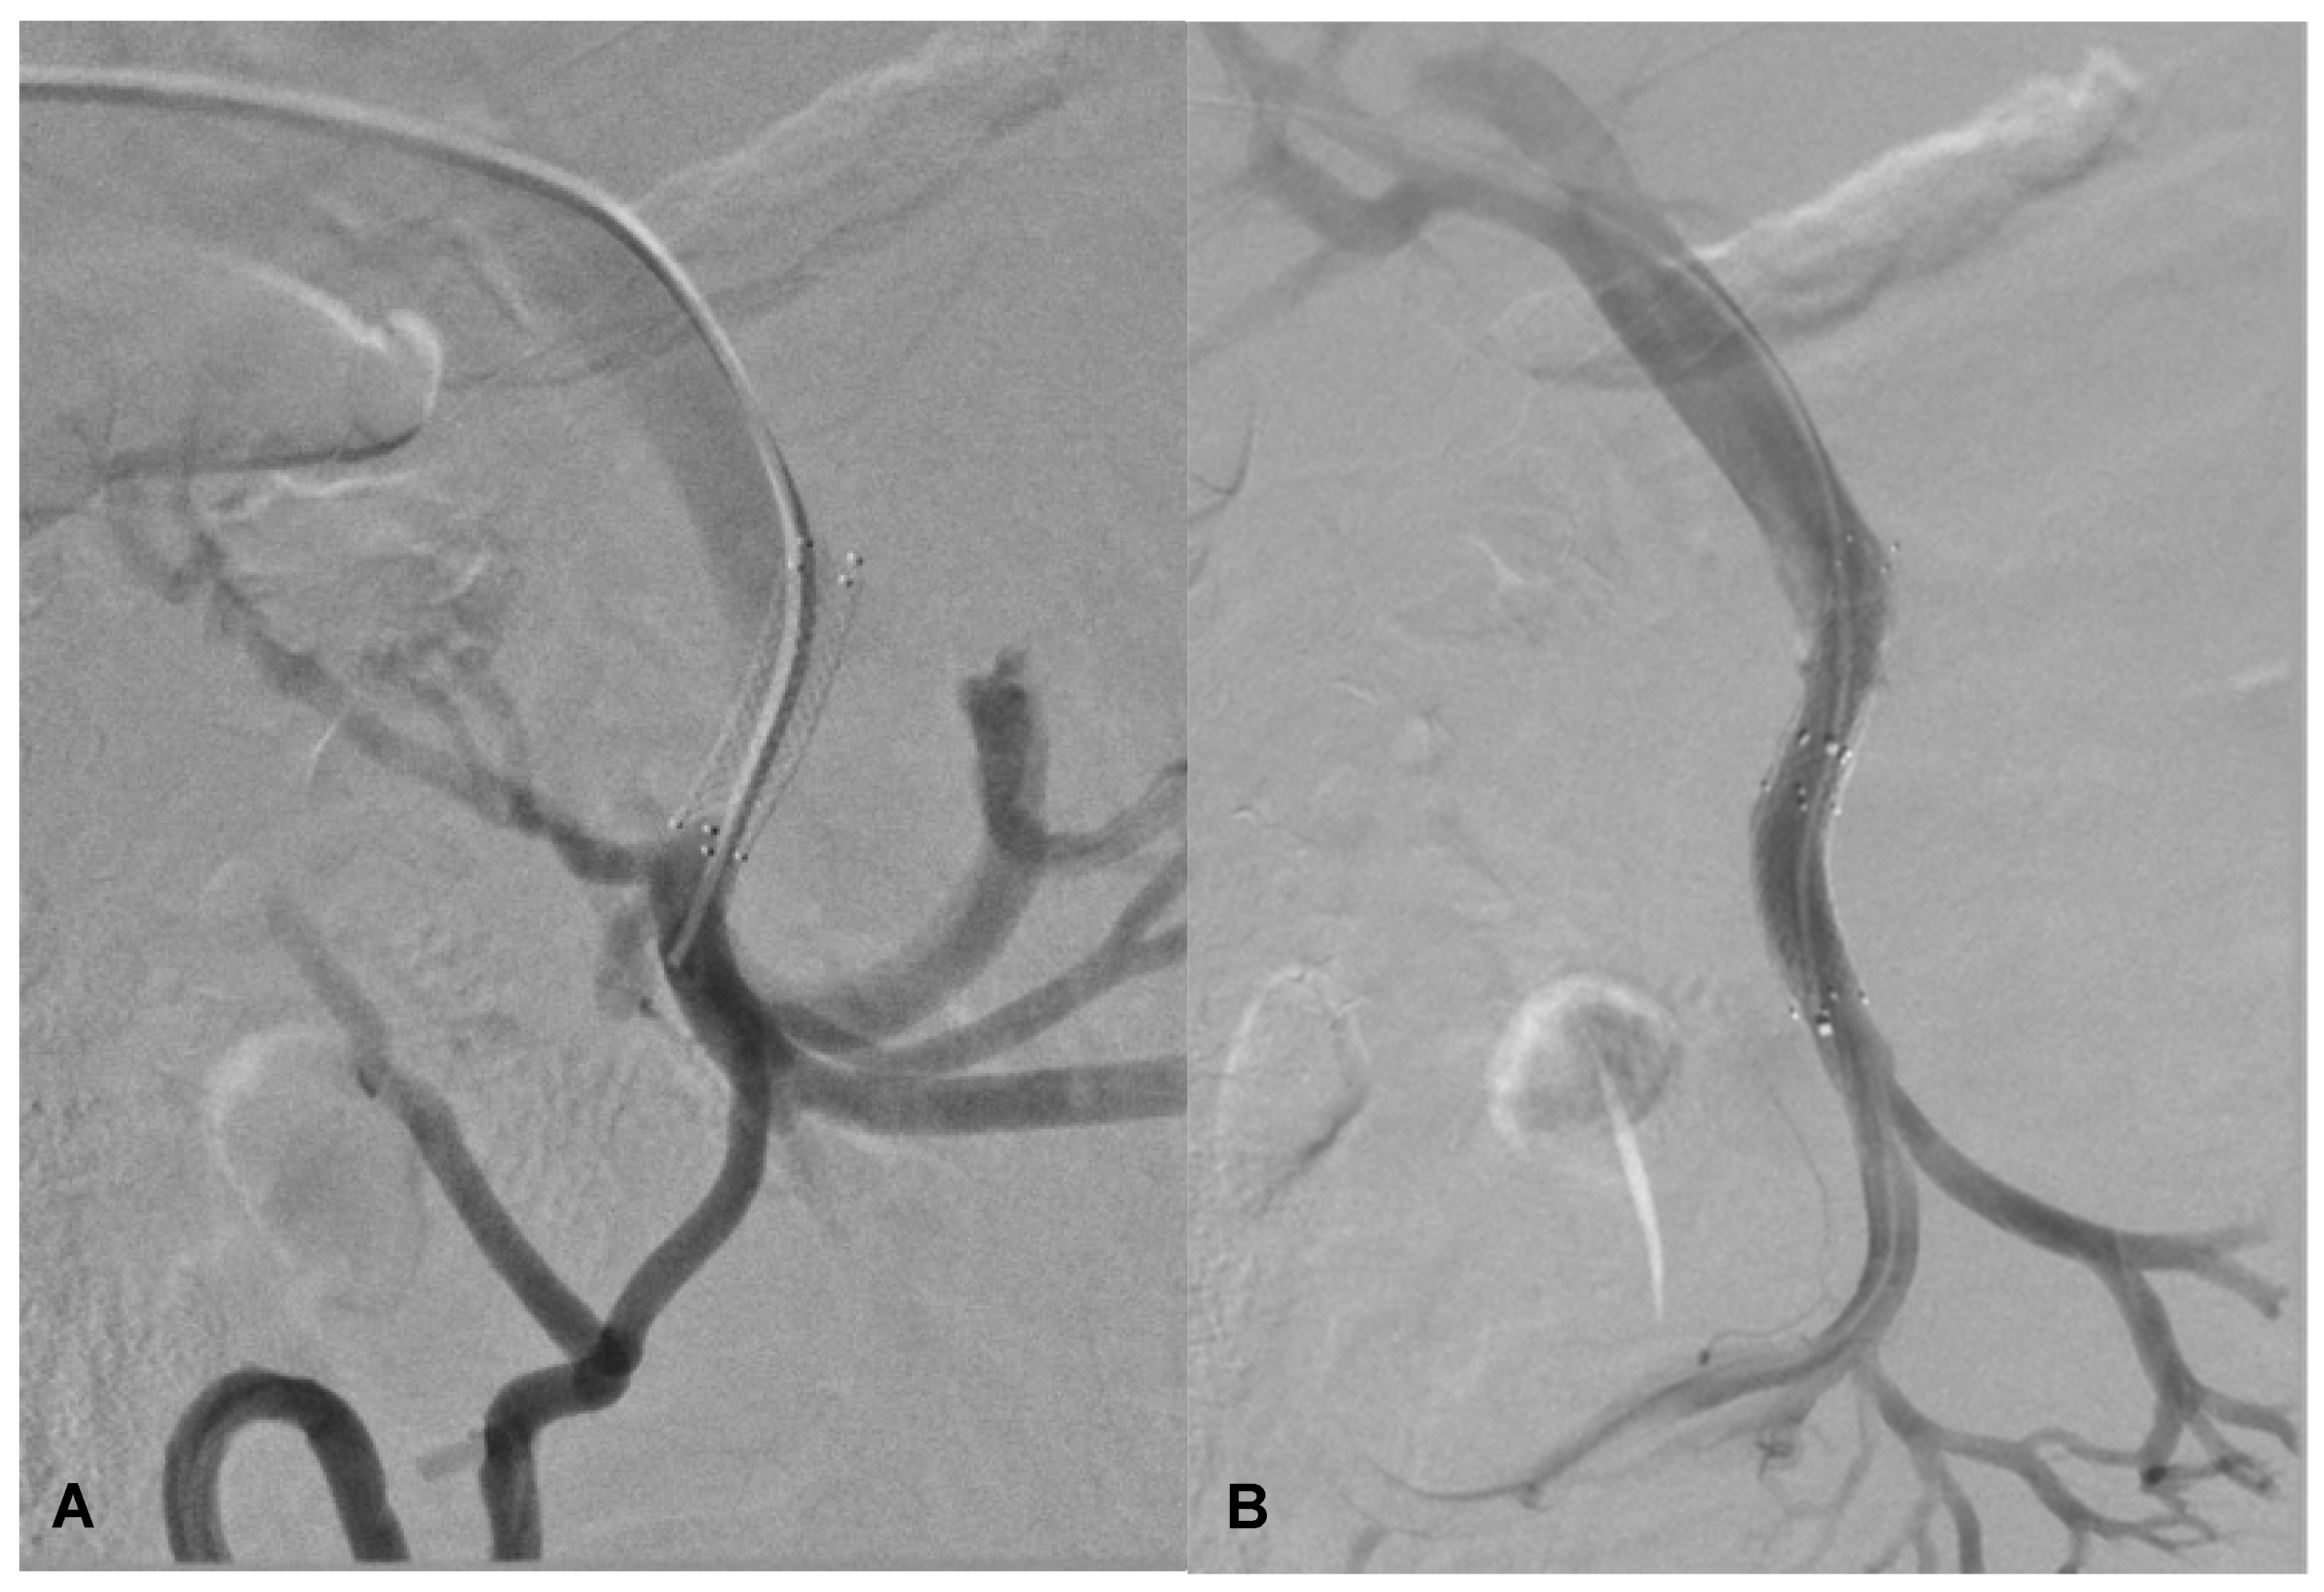

2. Case Report